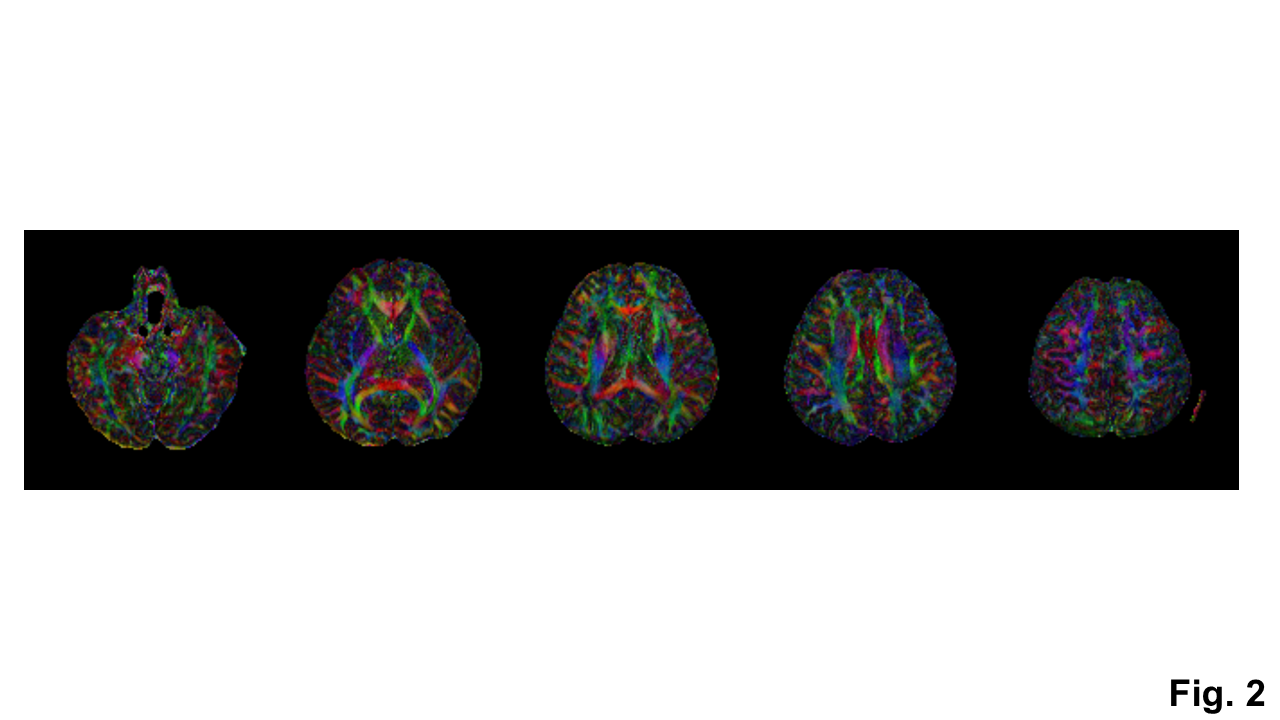

With the phase correction, the signal drop in DWI images was mitigated (Fig. 1b). The remaining slab boundary artifacts were reduced by using NPEN for combining slab images (Figs. 1a and 1b). Following the phase correction and NPEN, the 3D multi-slab DWI images for DTI measurements were used to generate color-coded FA maps (Fig. 2). For DKI measurements, the 3D multi-slab DWI images showed a higher SNR than the 2D DWI images (Fig. 3). The benefit of SNR was demonstrated by the mean kurtosis maps (Fig. 4). The mean kurtosis maps obtained by the 3D multi-slab DWI were more smooth in white-matter regions than those obtained by the 2D DWI. However, many zeros (negative kurtosis) were present on the mean kurtosis maps mainly at the gray matter–white matter and gray matter–CSF interfaces, likely caused by the partial volume effects. In the 3D multi-slab DWI, negative kurtosis may also result from the procedure for correcting the motion-induced phase errors. The self-navigation correction method17 relies on the smooth phase differences between b0 and DWI images to estimate the motion-induced phase. The choice of the smoothing kernel may result in incomplete removal of the phase errors or undesirable removal of the phases related to structural variations9,20,23. Future work is to increase the image resolution to reduce the partial volume effects and structure-related phases, and allow a more complete removal of the phase errors.

Fig. 2: Color-coded FA maps generated from the DTI measurements using the 3D multi-slab DWI shown in Fig. 1.